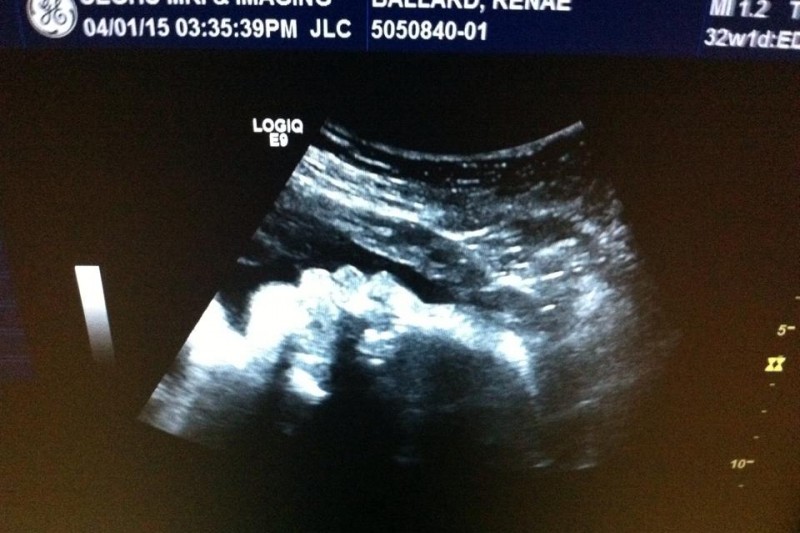

Renae and Ben Ballard are a couple from Savannah, Georgia with a 17 month old son and another son on the way. Renae and Ben found out April 21st, 2015 that their unborn son, Brantley David Ballard, has a congenital heart defect called Hypoplastic Left Heart Syndrome (HLHS). Since finding this out, Renae is required to have to deliver baby Brantley in Atlanta, Georgia at Northside hospital. Soon after delivery, Brantley will then be transferred over to the children’s hospital in Emory where he will then undergo a number of open heart surgeries.

Let me tell you a little bit more about Hypoplastic Left Heart Syndrome. HLHS is a rare congenital heart defect in which the left ventricle of the heart is severely underdeveloped. This syndrome affects normal blood flow through the heart. With HLHS, the left side of the heart does not form correctly during pregnancy. Most of the structures on the left side of the heart are too small and underdeveloped to provide enough blood flow for the body’s needs. The small left ventricle, which needs to be large enough and strong enough to pump blood out to the body, simply can’t function effectively. Other left heart structures can also be underdeveloped in varying degrees. The causes of Hypoplastic Left Heart Syndrome are unknown. HLHS occurs in one out of 4, 344 live births, or an estimated total of 960 live births every year in the United States.